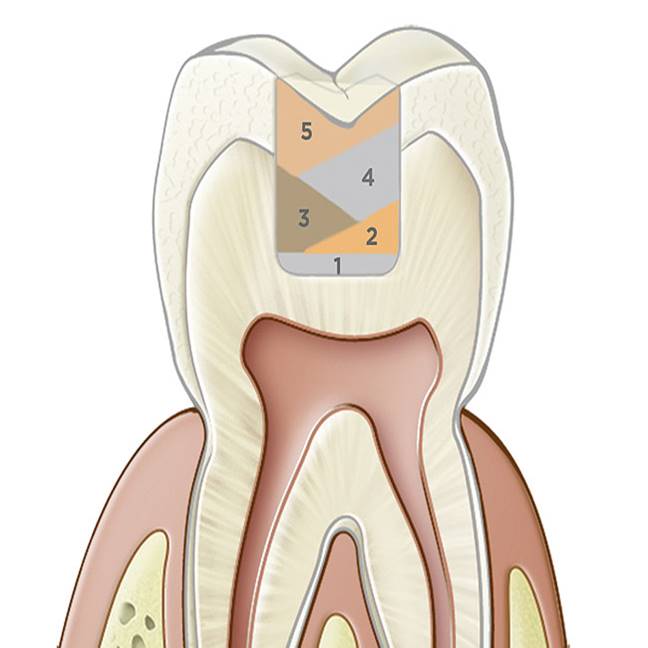

The most common problems associated with direct composite restorations include the time- and labor-intensive nature of the layering techniques involved with their placement, issues surrounding material adaptation, difficulty achieving tight contacts, polymerization and volumetric shrinkage, postoperative sensitivity, and microleakage leading to secondary caries.1,2 Composite layering protocol is dependent on restoration depth. Contributing to the time-intensive and technique-sensitive nature of multiple-layer restorations are the challenges encountered when ensuring that all composite layers combine properly and adapt well to each other and cavity walls, without producing porosities and voids (Figure 1).3

The reason composites must be layered and adapted to each other and cavity walls is to reduce the shrinkage stress produced during polymerization due to a restoration’s shape (ie, configuration [C]-factor). This C-factor, which is defined as the ratio of the restoration’s bonded to unbonded (ie, free) surfaces, influences the integrity of the composite/adhesive bonding to dentin. The fewer surfaces that are engaged by a composite increment at one time (eg, two surfaces), the lower the C-factor, the greater the bond strength, and the lower the amount of shrinkage stress there will be.4,5

Fig 1. Typically for preparations > 2 mm, numerous layers of composite must be placed into the preparation to diminish polymerization shrinkage and stresses on tooth structure.

Figure 1